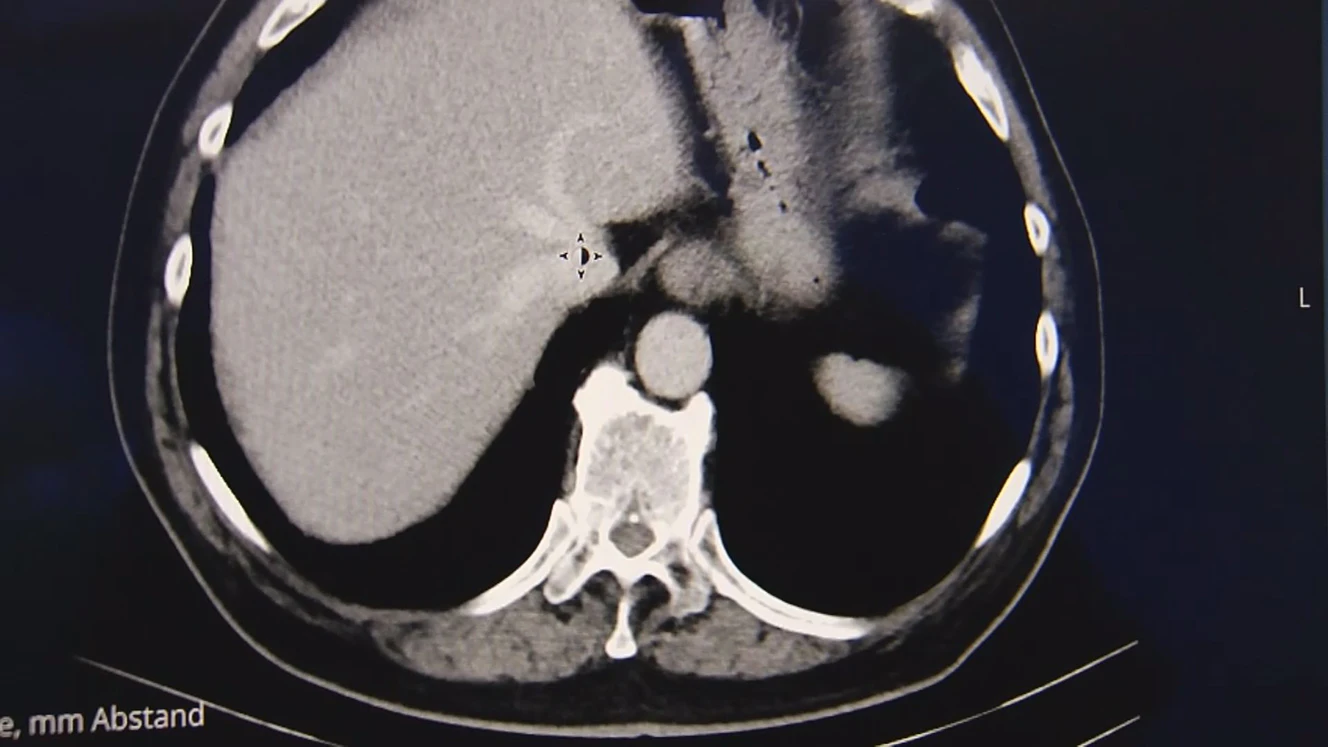

Weiden: Gemeinsam gegen den Krebs

Krebs ist laut dem Robert-Koch-Institut die zweithäufigste Todesursache in Deutschland. Jährlich erkranken hundertausende Menschen an Krebs. Die Fallzahlen nehmen zu, auch deswegen, weil die Menschen immer älter werden. Praktisch jeder von uns ist schon direkt oder indirekt mit Krebs in Berührung gekommen.

Aber es zeigt sich auch, die Sterblichkeitsrate sinkt stetig. Immer bessere und immer mehr Angebote gibt es für Betroffene. Doch das richtig zu finden und auch zu bekommen, ist keine leichte Aufgabe. Im Internet gibt es tausende Foren, die sich mit der Frage beschäftigen „Diagnose Krebs – Was nun?“. Das onkologische Zentrum in Weiden beantwortet diese Frage allumfassend und ist dafür zertifiziert worden.

Im Rahmen eines Festaktes in der Weidener Max-Reger-Halle wurde der Einrichtung der Kliniken Nordoberpfalz AG das Zertifikat der Deutschen Krebsgesellschaft übergeben. Seit 10 Jahren wird das onkologische Zentrum aufgebaut. Allumfassend und interdisziplinär sollen die Krebserkrankten dort betreut werden, erfuhren die Gäste beim Festakt in der Weidener Max-Reger-Halle. Seine Struktur ist deshalb weit verzweigt. Die Grundsäulen sind das Prostatakrebs-Zentrum, das Brustkrebszentrum und das viszeralonkologische Zentrum. Diese drei Zentren wiederrum arbeiten mit vielen Einrichtungen in der Region zusammen. Beispielsweise mit der Ernährungsberatung, mit Psychologen oder mit Sanitätshäusern. Die Zertifizierung jedenfalls habe nur Vorteile für den Patienten. (eg)